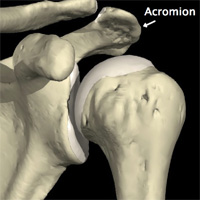

La rupture de la coiffe des rotateurs est souvent le stade ultime d’une tendinite de la coiffe des rotateurs. En effet, avant de se rompre, les tendons frottent sous l’acromion (bec osseux se situant juste au-dessus de l’épaule) réalisant le classique tableau de conflit sous-acromial.

Frottement des tendons sous l’acromion